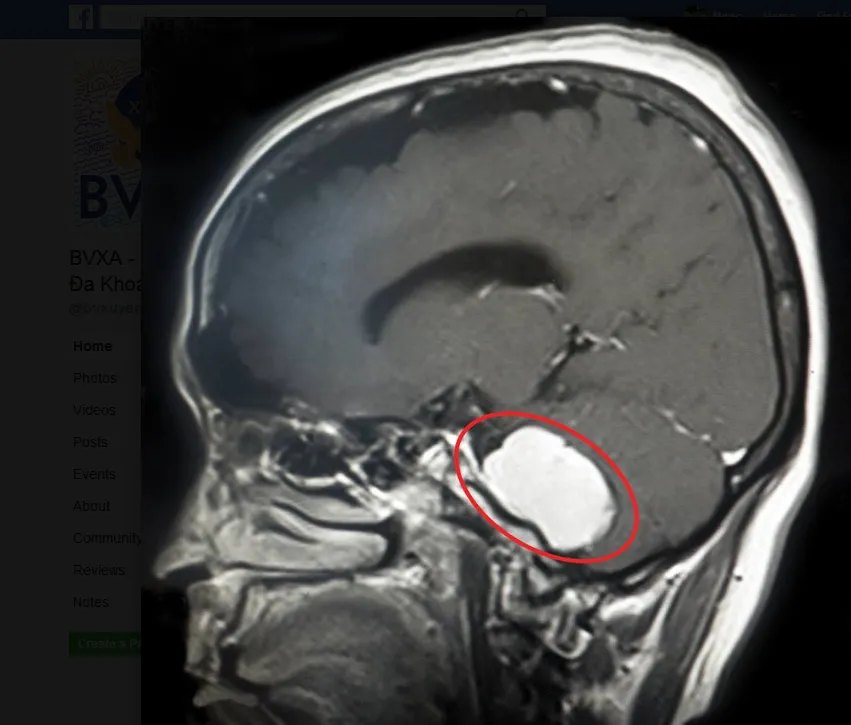

Trong quá trình phẫu thuật, các BS hết sức thận trọng và tỉ mỉ giải phóng u. Đồng thời tách u ra khỏi mạch máu thần kinh để hạn chế sang chấn thương chức năng của thân não và các dây thần kinh sọ não. Sau hơn bốn giờ, ca phẫu thuật đã thành công. Hiện sức khỏe bệnh nhân đã ổn định.

Các bác sĩ đang phẫu thuật khối u não cho bệnh nhân. Ảnh: LÊ PHỤNG